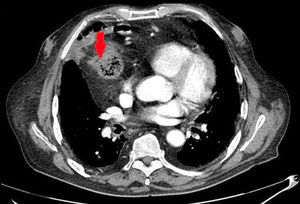

Presently, because of progressive dysphagia, an endoscopy study was ordered, which found a neoplasm 30cm from the dental arch. Biopsy identified the mass as a moderately differentiated intestinal adenocarcinoma. The extension study result was cT3N0 (Fig. 1). We performed a surgical approach with iterative cervicotomy, median sternotomy and midline laparotomy, followed by exeresis of the coloplasty. The digestive tract reconstruction was done with a “supercharged” jejunal segment that was provided with additional blood flow by means of anastomosis of the jejunal vein and artery to the left internal mammary vessels. The digestive anastomoses included an end-to-side oesophagojejunostomy and a side-to-side jejunojejunostomy on the Roux-en-Y loop of the former coloplasty.